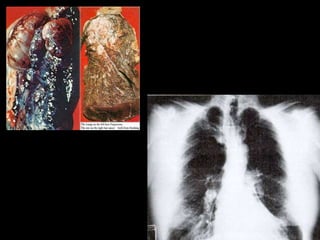

Câncer pulmonar.  câncer de pulmão é o mais comum dos tumores malignos, apresentando um aumento por ano de 2% na sua incidência mundial. A mortalidade por esse tumor é muito elevada e o prognóstico dessa doença está relacionado à fase em que é diagnosticada.

Enfisema e pulmonar É uma doença crônica, na qual os tecidos dos pulmões são gradualmente destruídos, tornando-se hiperinsuflados (muito distendidos).  Esta destruição ocorre nos alvéolos, onde acontece a troca gasosa do oxigênio pelo dióxido de carbono. Como resultado, a pessoa passa a sentir falta de ar para realizar tarefas ou exercitar-se.  Nas áreas destruídas, não ocorrem as trocas gasosas de maneira satisfatória, fazendo com que diminua a quantidade de oxigênio circulante no sangue e, então, surge a falta de ar . Na maioria das vezes, são tabagistas de longa data, que, em torno dos 65 anos de idade, passam a sentir falta de ar para fazer esforços. A falta de ar no início só é notada para os grandes e médios esforços (subir escadas ou caminhar são exemplos). Mantendo o hábito do fumo, poderão chegar a uma fase mais avançada da doença, em que falta de ar surge com tarefas simples como tomar banho, se vestir ou se pentear, por exemplo.

Tabagismo  O tabagismo pode degradar o sistema respiratório,causando diversos males ao mesmo: Pode causar a irritação dos brônquios provocando infecções, Principal causador de câncer pulmonar,cerca de 69% dos casos são detectados em fumantes ou em pessoas que são ex-fumantes. Causador de doenças como insuficiência respiratória e enfisema pulmonar,e dificuldades de respiração devido a concentração de nicotina e outras substâncias nos pulmões

Enfisema e pulmonarÉ uma doença crônica, na qual os tecidos dos pulmões são gradualmente destruídos, tornando-se hiperinsuflados (muito distendidos). Esta destruição ocorre nos alvéolos, onde acontece a troca gasosa do oxigênio pelo dióxido de carbono. Como resultado, a pessoa passa a sentir falta de ar para realizar tarefas ou exercitar-se. Nas áreas destruídas, não ocorrem as trocas gasosas de maneira satisfatória, fazendo com que diminua a quantidade de oxigênio circulante no sangue e, então, surge a falta de ar . Na maioria das vezes, são tabagistas de longa data, que, em torno dos 65 anos de idade, passam a sentir falta de ar para fazer esforços. A falta de ar no início só é notada para os grandes e médios esforços (subir escadas ou caminhar são exemplos). Mantendo o hábito do fumo, poderão chegar a uma fase mais avançada da doença, em que falta de ar surge com tarefas simples como tomar banho, se vestir ou se pentear, por exemplo.

Tabagismo Otabagismo pode degradar o sistema respiratório,causando diversos males ao mesmo: Pode causar a irritação dos brônquios provocando infecções, Principal causador de câncer pulmonar,cerca de 69% dos casos são detectados em fumantes ou em pessoas que são ex-fumantes. Causador de doenças como insuficiência respiratória e enfisema pulmonar,e dificuldades de respiração devido a concentração de nicotina e outras substâncias nos pulmões